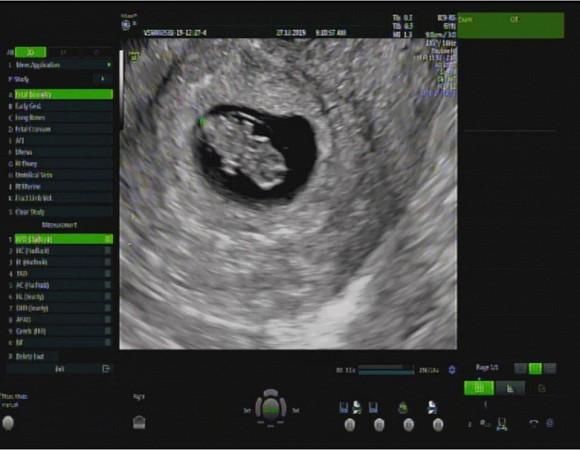

Hình ảnh siêu âm được Vân Navy chia sẻ với fan.